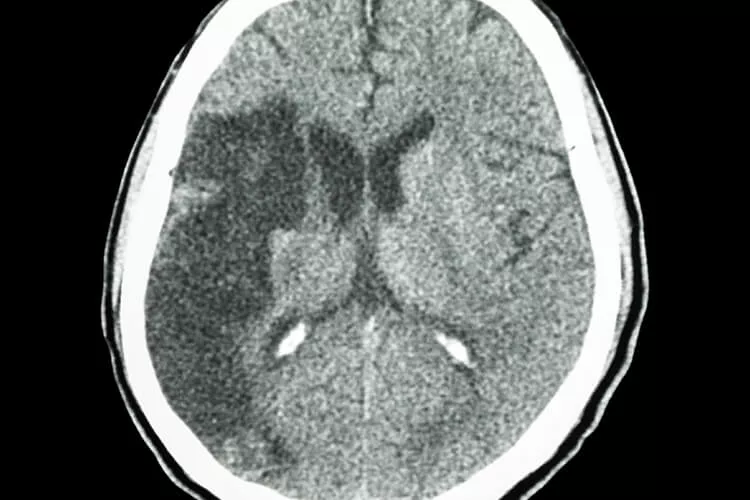

Ilustrační obrázek

Nediagnostikovaná neurogenní patologie (například nesynchronicita svěračů či hypoaktivita detruzoru močového měchýře) se samozřejmě může projevit i ve výsledcích urodynamického vyšetření či na uroflowmetru – například již slabším proudem moči při mikci nebo reziduem moči po vymočení. Pozorná analýza urodynamického vyšetření se též doporučuje u mužů s výraznými LUTS a menší prostatou – odhalením neurologické poruchy je možné předejít zbytečnému operačnímu zákroku. A u suspektních případů není nikdy zbytečné odeslat pacienta k neurologickému vyšetření – ať již kognitivních funkcí, nebo struktur a funkcí nervového systému (magnetickou rezonancí, výpočetní či pozitronovou emisní tomografií). Popřípadě je na místě provedení laboratorních nebo i jiných rozborů.